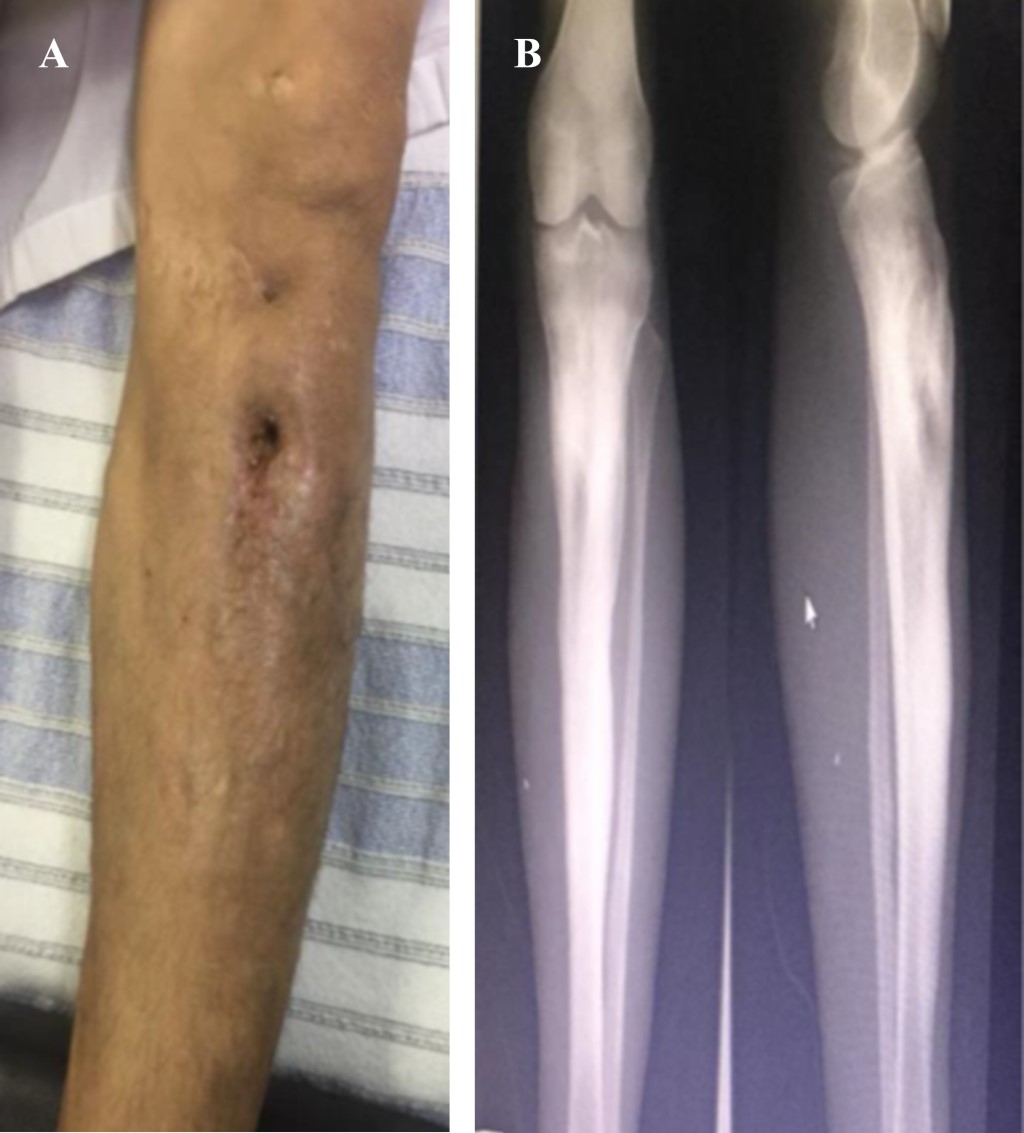

En el segundo tiempo quirúrgico se realiza toma de peroné libre no vascularizado, se fija y estabiliza con tornillos 4.5 de titanio con colocación de cuatro tornillos de una medida estándar de 30 mm, posteriormente se coloca el vidrio bioactivo en zonas de interface entre peroné estabilizado y cortical posterior de tibia en toda su longitud así como llenado total de cavidad medular en región metafisaria, (se utilizaron 16 g de vidrio bioactivo de 1 mm), se cierra herida quirúrgica y se le mantiene hospitalizado, se aplica amikacina 250 mg c/12 horas y moxifloxacino 400 mg cada 24 horas. Egresa del hospital cinco días después de segunda intervención quirúrgica con herida en fase de cicatrización, fístulas cerradas sin gasto, se indica antibiótico moxifloxacino 400 mg vo cada 24 horas, por seis meses y controles de pruebas de función hepática mensuales. Se valora un mes después, presenta heridas quirúrgicas limpias cicatrizadas, fístulas cerradas sin datos de infección, arcos de movimiento completos, hipotrofia muscular, control radiográfico con injerto en fase de integración sin datos de inestabilidad de material de osteosíntesis, PFH en parámetros normales, se continúa con moxifloxacino 400 mg cada 24 horas y ejercicios de rehabilitación. Última valoración tres meses después, el paciente ya camina sin apoyo y pruebas de laboratorio dentro de parámetros normales (Figura 3).

Figura 3